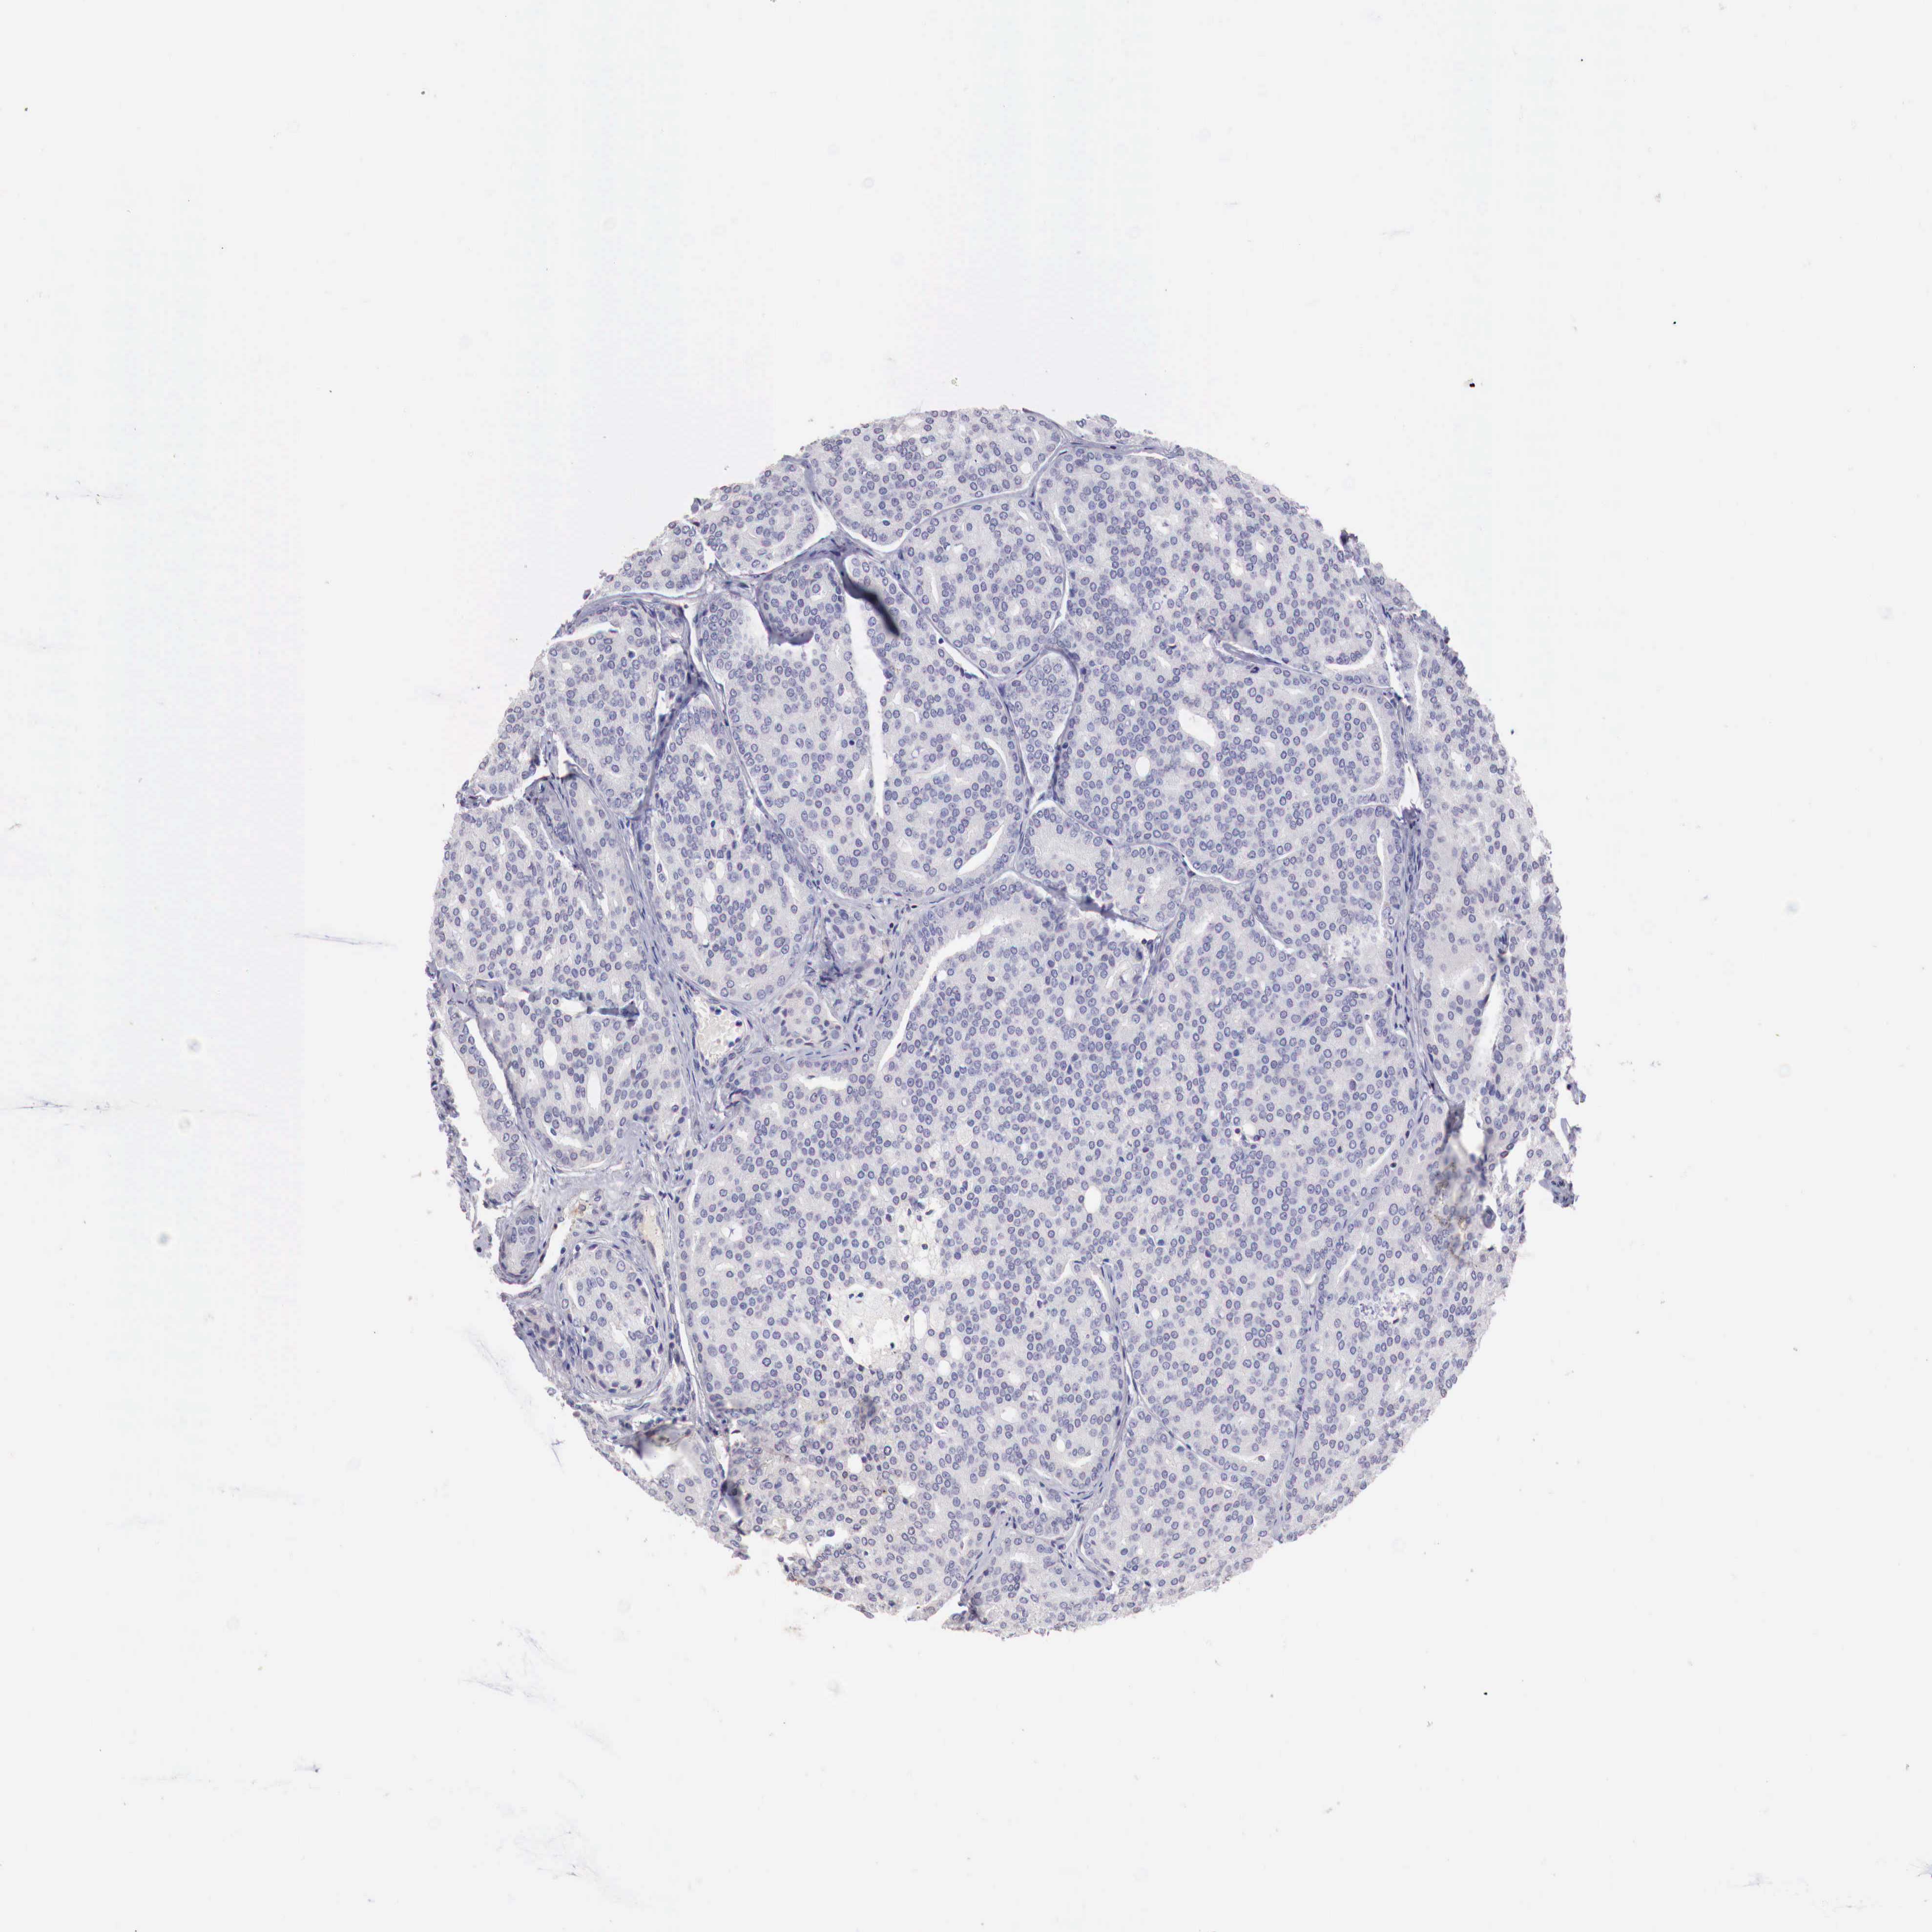

PROSTATE CANCER - Protein expressioni

A mouse-over function shows sample information and annotation data. Click on an image to view it in a full screen mode. Samples can be filtered based on level of antibody staining by selecting one or several of the following categories: high, medium, low and not detected. The assay and annotation is described here.

Note that samples used for immunohistochemistry by the Human Protein Atlas do not correspond to samples in the TCGA dataset.

Antibody stainingi

Antibody staining in the annotated cell types in the current human tissue is reported as not detected, low, medium, or high, based on conventional immunohistochemistry profiling in selected tissues. This score is based on the combination of the staining intensity and fraction of stained cells.

Each image is clickable and will lead to virtual microscopy that enables deeper exploration of all samples and also displays staining intensity scores, fraction scores and subcellular localization as well as patient and tissue information for each sample.

Antibody CAB025269

Staining

High

Medium

Low

Not detected

Intensity

Strong

Moderate

Weak

Negative

Quantity

>75%

75%-25%

<25%

None

Location

Nuclear

Cytoplasmic/membranous

Cytoplasmic/membranous,nuclear

Adenocarcinoma, Medium grade

Adenocarcinoma, Low grade

Adenocarcinoma, High grade

Adenocarcinoma, NOS